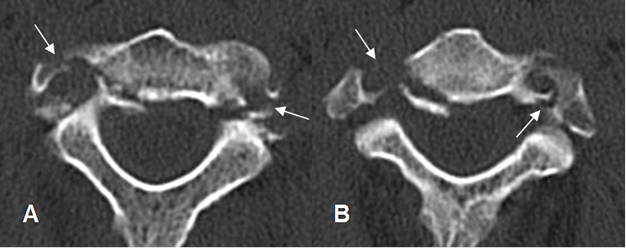

Fig 211 A. Fractura de foramen vertebral.

A y B: TAC axial. Fractura de los agujeros vertebrales a nivel bilateral, con diferente grado de desplazamiento y conminución.

Fig 211 B. Trauma vascular.

TAC axial. Fractura no desplazada de la lámina izquierda. (Flecha delgada). Ausencia de contraste en el foramen vertebral del mismo lado, por lesión vascular asociada. (Flecha gruesa). Arterias carótidas y vertebral derecha, de aspecto normal.